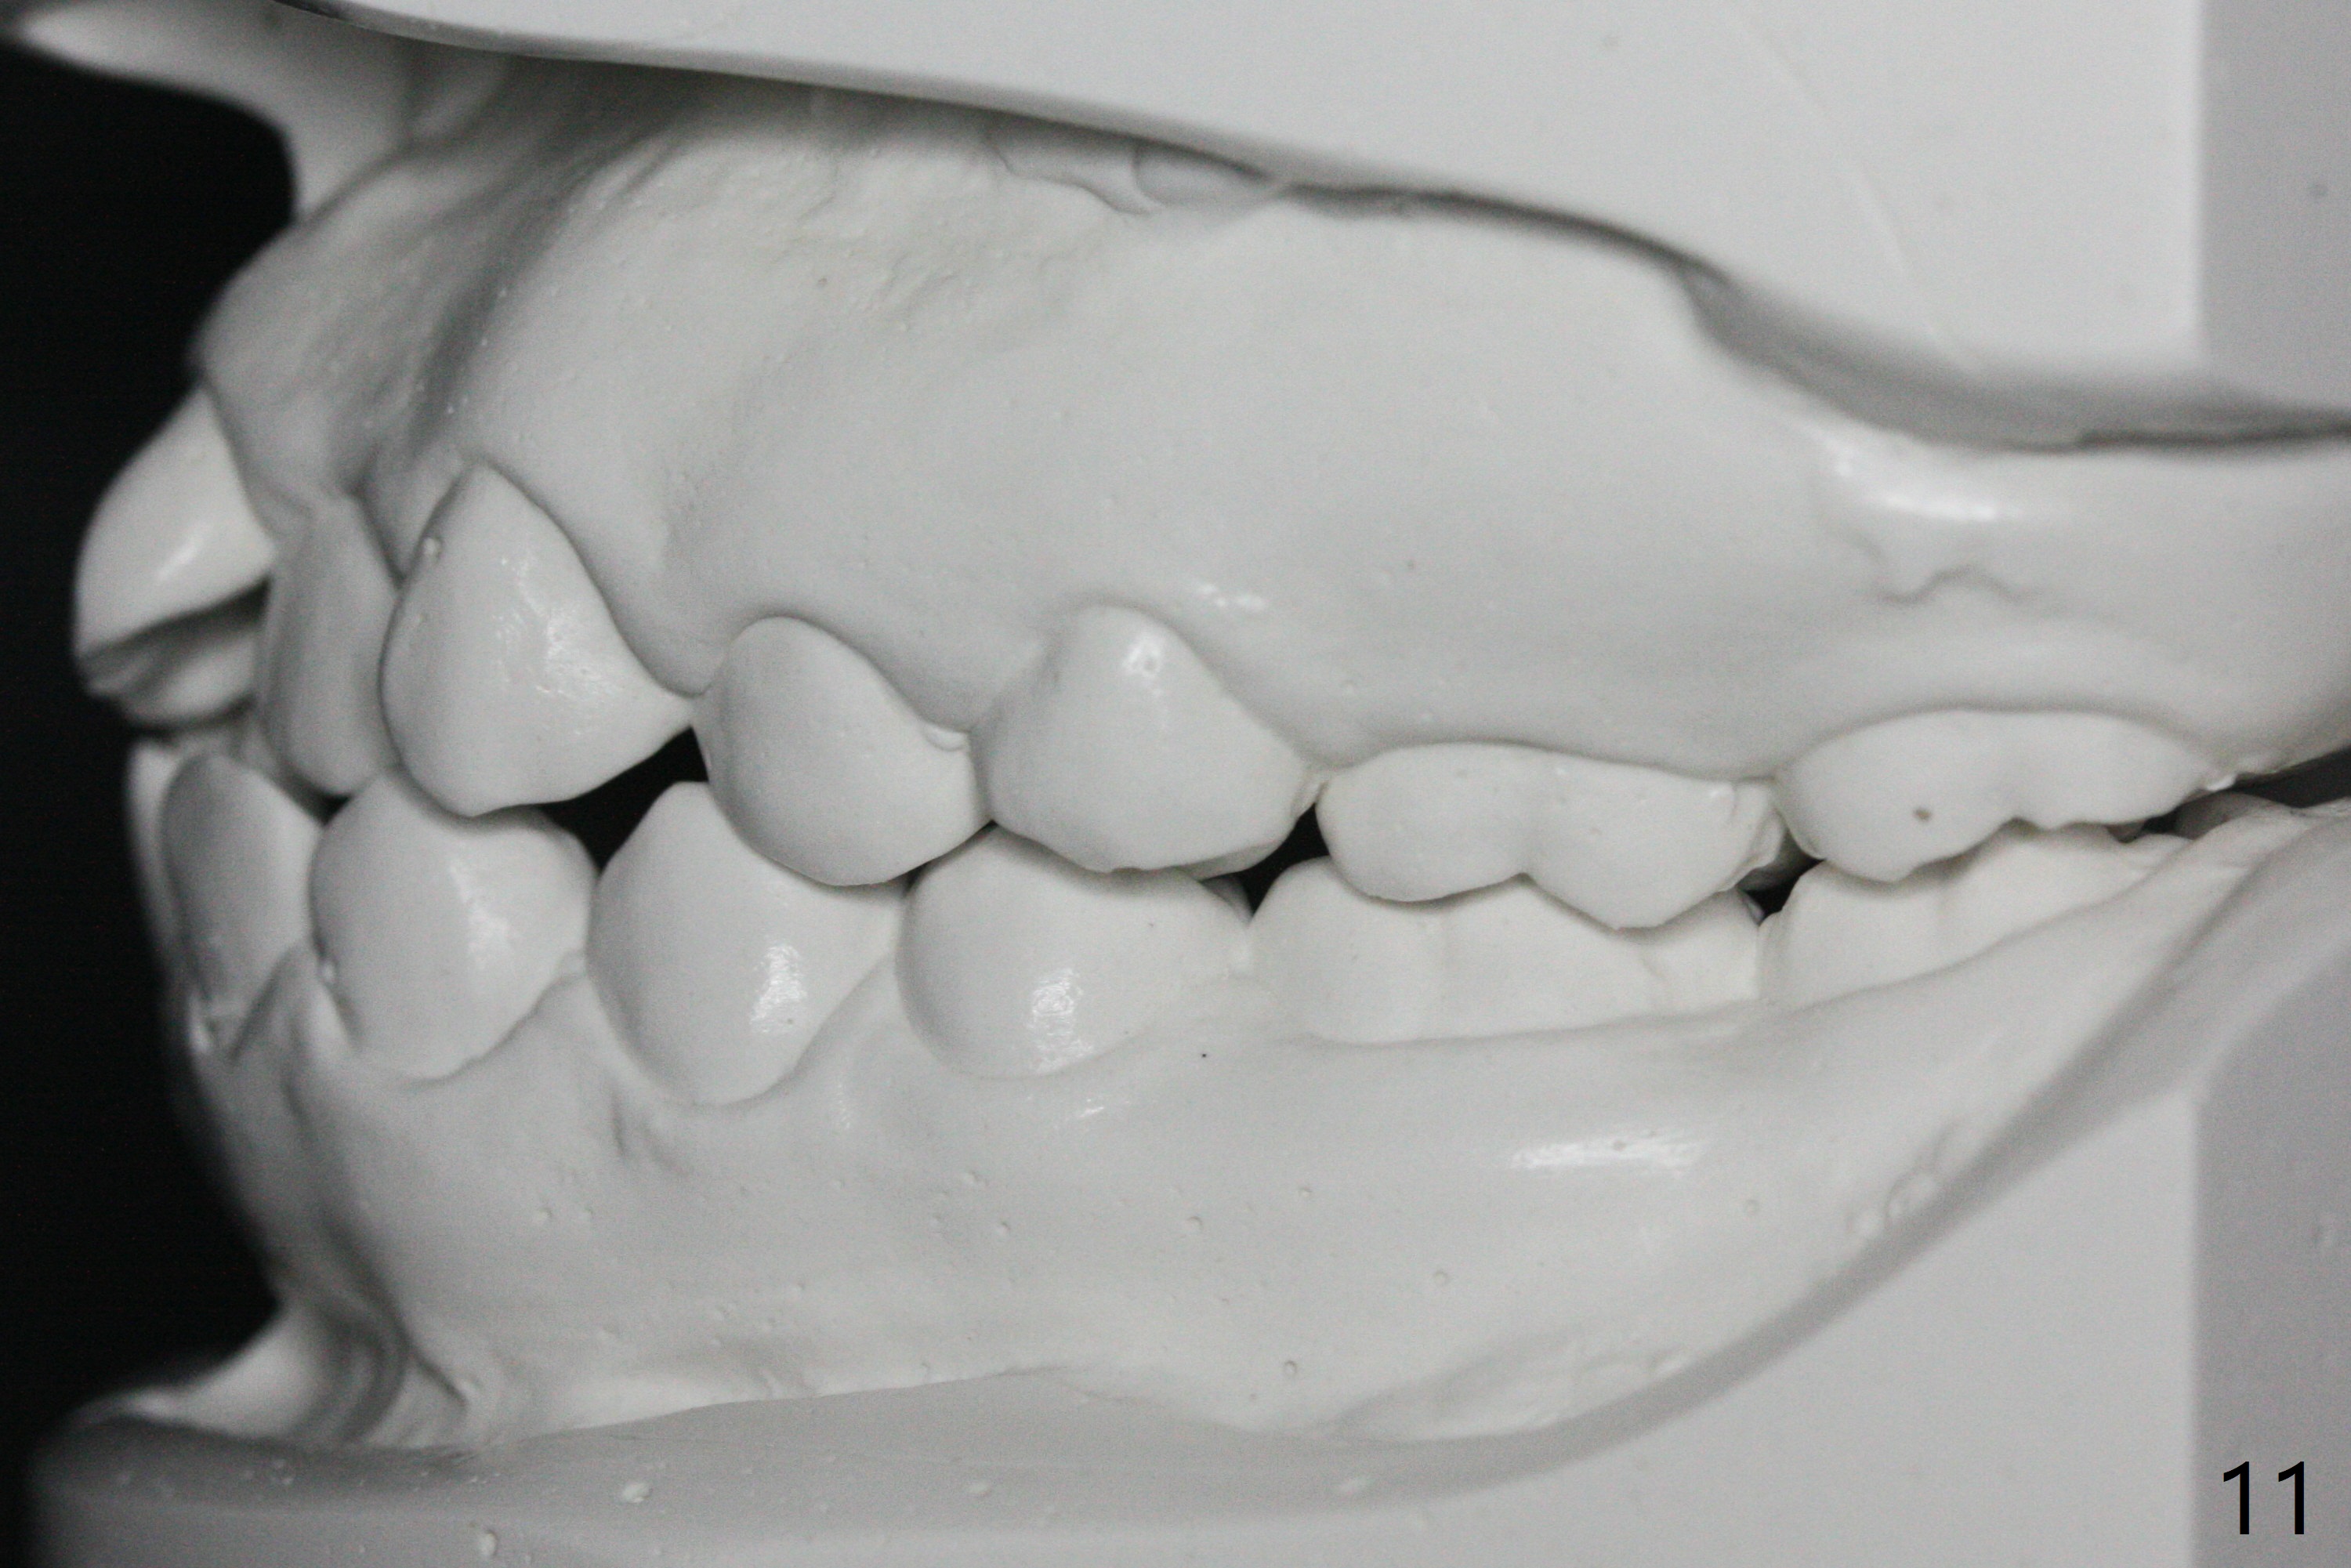

A 14-year-old woman has convex facial profile (Fig.1-4) with the upper midline shifted to the left (Fig.2). Since the roots of the 1st bicuspids are short (Fig.5), extraction should be easy. U3 will be retracted distal early with intention to correct the upper midline. With Class I occlusion at the canines and the 1st molars and good initial interdigitation (Fig.6-11), orthodontic treatment should be rewarding. Because of severe crowding (tight contact, Fig.12,13), place separators after extraction and place bands and brackets a few days later. Cephalometric analysis (Fig.14) shows that SNB is greater than SNA (82.4 vs. 81.8 degree); after extraction, retract the lower anterior teeth prior to the upper ones. It is easy to place separators after extraction (Fig.16,17).